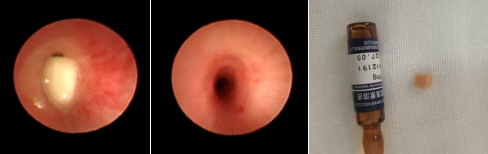

6月9日夜间,一名心急如焚的家长急匆匆抱着1岁3月幼童来到我院急诊科,根据患儿家长描述,患儿2小时前食用馍夹菜后出现呛咳,继之阵发性咳嗽、喘息,应元杰主治医师接诊后,根据多年的工作经验,考虑患儿为支气管异物。经过仔细查体和胸部CT检查,确诊患儿为支气管异物。考虑患儿已进食进水,目前生命体征平稳,为保证患儿取异物时的安全性,给予禁食水后,于6月10日上午,漯河市中心医院儿三病区(小儿呼吸二病区)主任韩传映副主任医师带领儿科支气管镜团队在儿童支气管镜检查室,于局部表面麻醉复合清醒麻醉下进行了异物取出术。术中左主支气管可见一长方形异物与气管紧密贴合,气管周围组织充血、水肿,应用网篮套取,成功将异物取出。

至此,导致患儿咳嗽、喘息的“真凶”终于找到了------“支气管异物--火腿肠”。